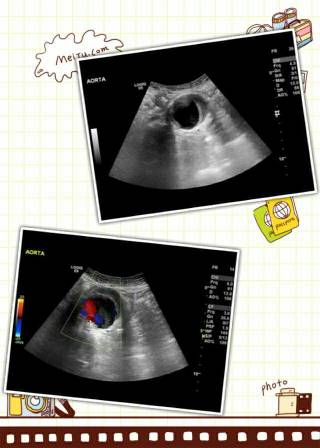

2.彩色多普勒超声

对腹主动脉瘤的诊断很有价值,探查动脉瘤的准确性高,可发现腹主动脉的管腔增粗,清晰地显示其外形及附壁血栓等,为目前优选的诊断方法。